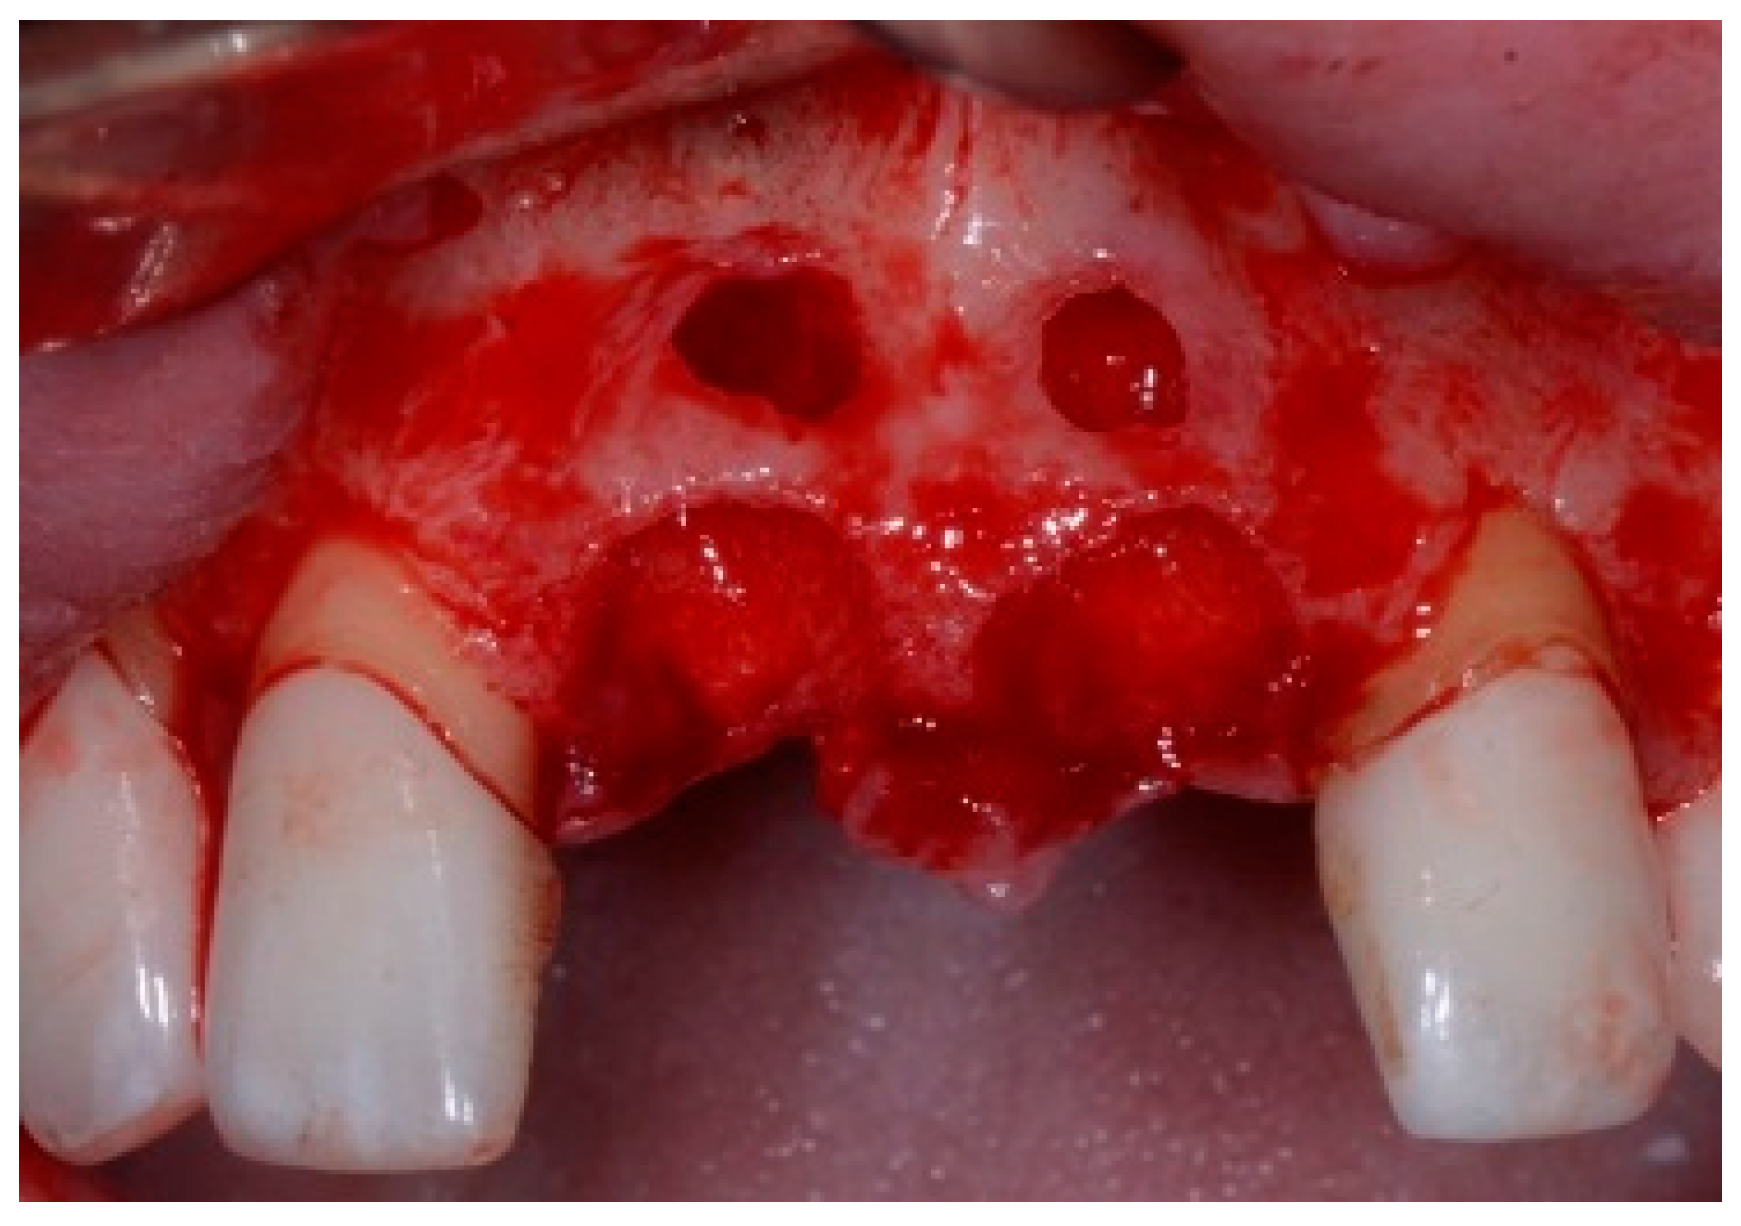

One hour before the surgical procedure, the patient received a prophylactic dose of 1 g of amoxicillin. Following local anesthesia, surgical access was obtained by raising a full-thickness aesthetic flap extending to the distal line angles of the lateral incisors. The full-thickness flap was extended 3–5 mm beyond the apical margin of the defect. The two central incisor roots were extracted, and the sockets were curetted with surgical curettes to remove all the granulation tissue (Figure 2). The sockets were assessed for the presence of a dehiscence and or fenestration. Two implants (Adin Dental Implants, Englewood, NJ, 07632, USA) were placed according to the manufacturer’s instructions (Figure 3).

Figure 2.

Clinical view immediately after extraction.